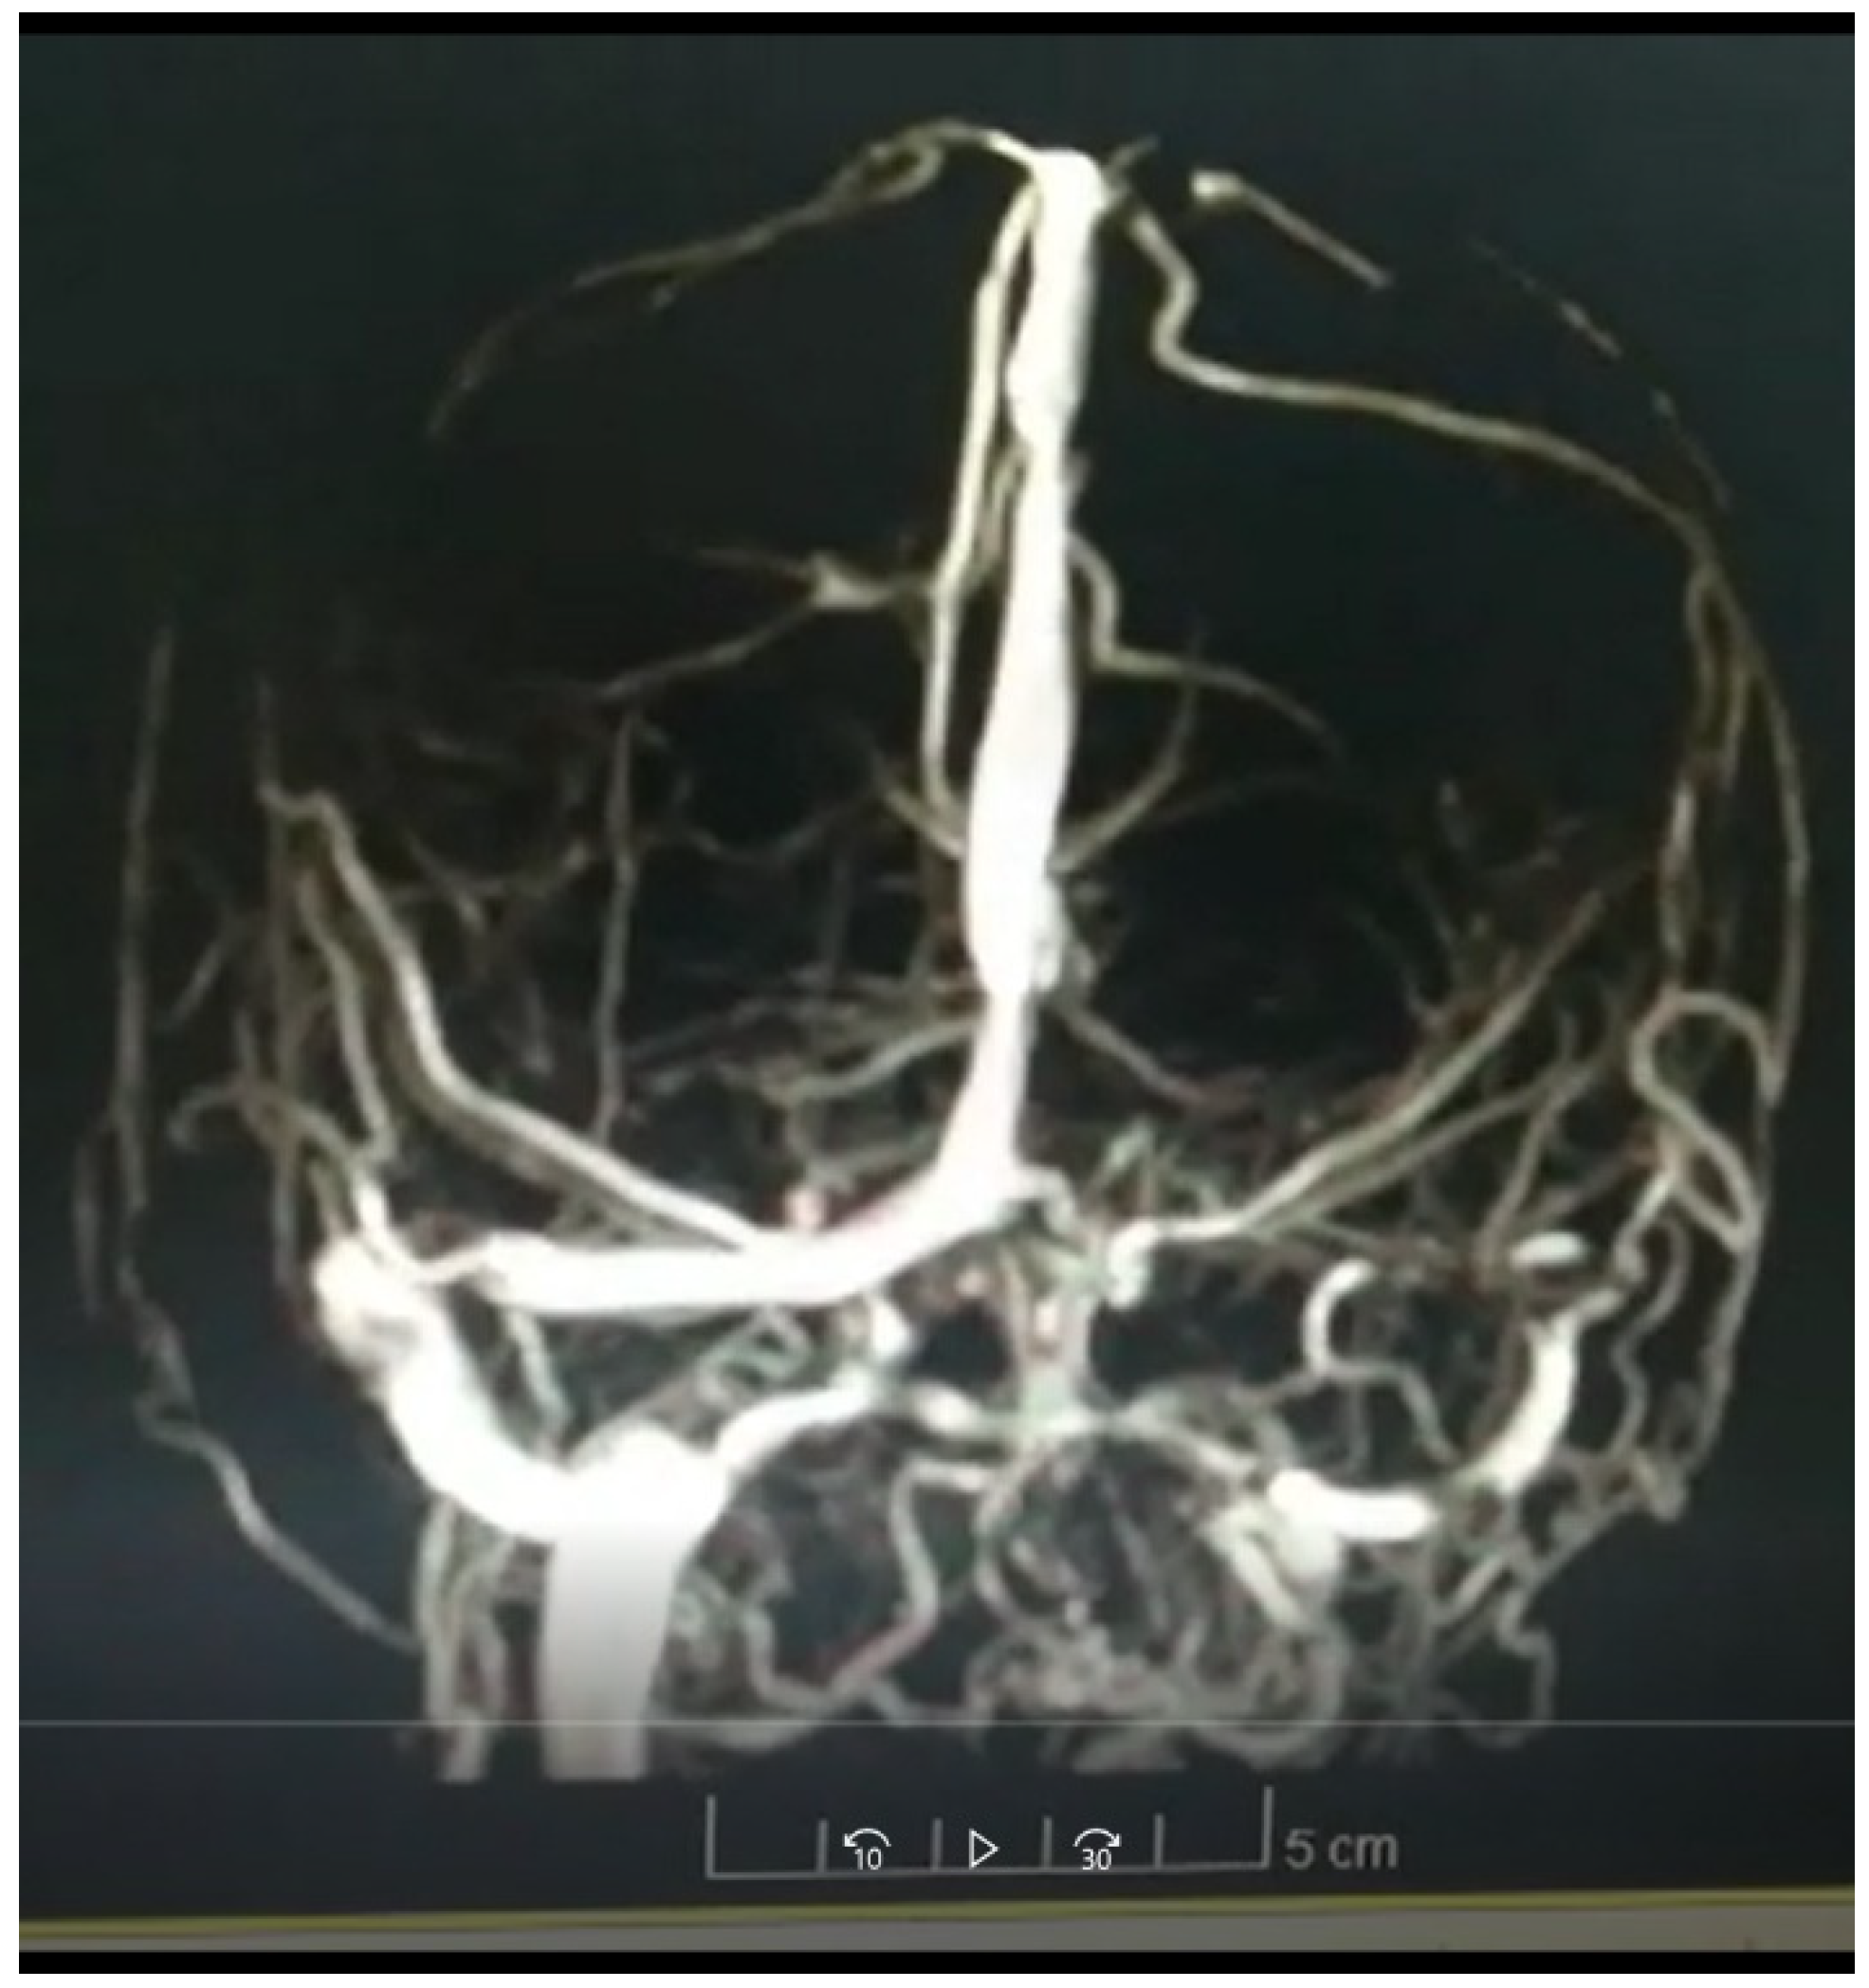

This is a 37-year-old female patient who presents after 11 days of vaccination with ChAdOx1-S agent against COVID-19 presents intense headache associated with symptoms of intracranial hypertension, after admission due to the aforementioned alarm symptoms and High blood pressure figures were initially taken to a simple cranial tomography showing the presence of cerebral edema and indirect signs of cerebral venous thrombosis.

Figure 1. Simple brain tomography performed on admission.